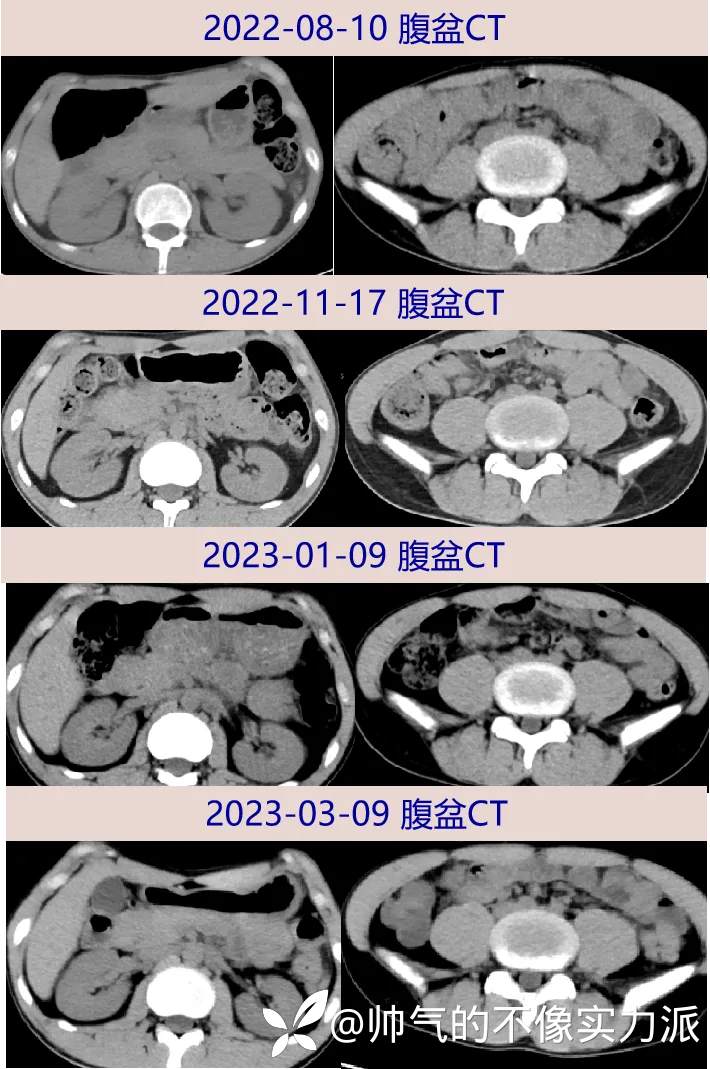

- 2022-08-10 复查胸部CT:两肺感染,考虑肉芽肿性病变累及胸膜;纵隔肿大淋巴结,两侧少量胸腔积液。腹盆CT:腹膜多发增厚,腹腔及腹膜后多发稍肿大淋巴结,腹盆腔少量积液,盆腔囊性灶,较2022-7-7片大致相仿。

- 2022-11-17 随访胸部CT:两肺感染,考虑肉芽肿性病变累及胸膜,较前22-08-10整体好转,个别新增或扩大。腹盆CT:腹膜多发增厚,腹腔及腹膜后多发稍肿大淋巴结,盆腔囊性灶较前22-08-10缩小,盆腔少量积液。左眼仍为失明状态,无疼痛、溢脓,眼科门诊随访建议结核感染控制后择期行整形手术。

- 2023-01-09 复查胸部CT:两肺感染,考虑肉芽肿性病变累及胸膜,纵隔肿大淋巴结,两侧少量胸腔积液,较前22-11-17总体好转。腹盆CT:腹膜多发增厚,腹腔及腹膜后多发稍肿大淋巴结,较前(22-11-17)好转。

- 2023-03-08 腹胀腹痛明显好转,逐步恢复正常饮食,未再发肠梗阻,无发热盗汗,体重较出院前增长12kg(身高170cm,体重52kg, BMI 17.9);随访WBC 7.26×10^9/L,N 55.9%,ESR 5mm/H,hs-CRP 10.8mg/L ;肾功能恢复正常, sCr 86μmol/L ;胸部CT:两肺感染,考虑肉芽肿性病变累及胸膜,纵隔肿大淋巴结,两侧少量胸腔积液,较前23-01-09稍有吸收。腹盆CT:腹膜多发增厚,腹腔及腹膜后多发稍肿大淋巴结,部分病灶较前23-01-09稍好转。